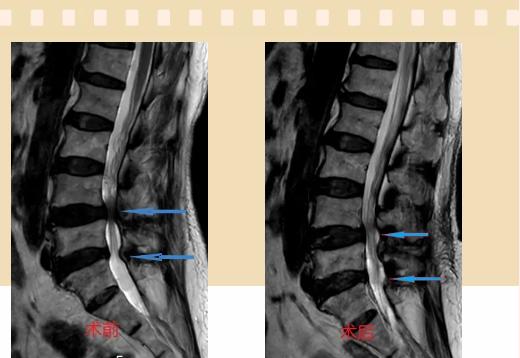

入院后李鵬副主任醫(yī)師為其進行了詳細的查體,完善了術(shù)前的檢查,明確診斷為:腰椎管狹窄癥(L4/5、L5/S1),病人合并2型糖尿病,請內(nèi)分泌科會診,穩(wěn)定血糖后,麻醉科會診病人,排除手術(shù)禁忌,李鵬為病人制定了手術(shù)方案:單側(cè)入路雙側(cè)減壓(ULBD)。

手術(shù)采用三個微創(chuàng)小切口,兩個節(jié)段減壓手術(shù)時間2.5小時,出血50ml。術(shù)后2天腰圍保護下床活動,術(shù)后5天順利出院。

傳統(tǒng)腰椎管狹窄癥的手術(shù)治療,往往需要切開減壓,同時需要內(nèi)固定融合術(shù),創(chuàng)傷很大,同時可能需要輸血,臥床時間較長,病人合并糖尿病,感染風(fēng)險也高,而本次采用的UBE-ULBD手術(shù)切口更?。悠饋砑s3cm,如果是單節(jié)段狹窄只需要不到2cm切口)、創(chuàng)傷更小,術(shù)后恢復(fù)較快,可以更早地恢復(fù)正?;顒印?/div>

此外,手術(shù)保留了病變節(jié)段的穩(wěn)定性,是一種微創(chuàng)的椎管減壓手術(shù),能通過切除部分椎板、關(guān)節(jié)突關(guān)節(jié)、黃韌帶來解除神經(jīng)根和硬膜囊的壓迫,不需要額外行腰椎內(nèi)固定術(shù),不需要螺釘及融合器的植入,病人術(shù)后腰椎的活動度不受影響。(盧 闖 劉 旭 袁錦鈺)